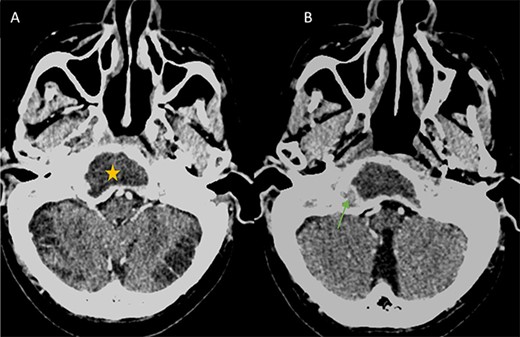

A computed tomography (CT) scan with intravenous contrast was performed (Figs 1 and 2), it revealed:

A 3 × 2.5 × 3.2 cm low-attenuating intra clival mass with peripheral enhancing, accompanied by extensive bone erosion of the clivus.

(A) Axial CT in soft-tissue window showing an intra clival fluid collection (star). (B) Axial Post contrast CT showing a peripheral enhancement (arrow).